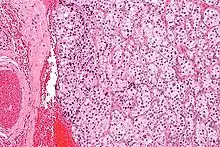

| Micrograph of a carotid body tumor (a type of paraganglioma). | |

On microscopic inspection, the tumor cells are readily recognized. Individual tumor cells are polygonal to oval and are arranged in distinctive cell balls, called Zellballen.[8] These cell balls are separated by fibrovascular stroma and surrounded by sustentacular cells.

By light microscopy, the differential diagnosis includes related neuroendocrine tumors, such as carcinoid tumor, neuroendocrine carcinoma, and medullary carcinoma of the thyroid.

With immunohistochemistry, the chief cells located in the cell balls are positive for chromogranin, synaptophysin, neuron specific enolase, serotonin, neurofilament and Neural cell adhesion molecule; they are S-100 protein negative. The sustentacular cells are S-100 positive and focally positive for glial fibrillary acidic protein. By histochemistry, the paraganglioma cells are argyrophilic, periodic acid Schiff negative, mucicarmine negative, and argentaffin negative.

Micrograph of a carotid body tumor